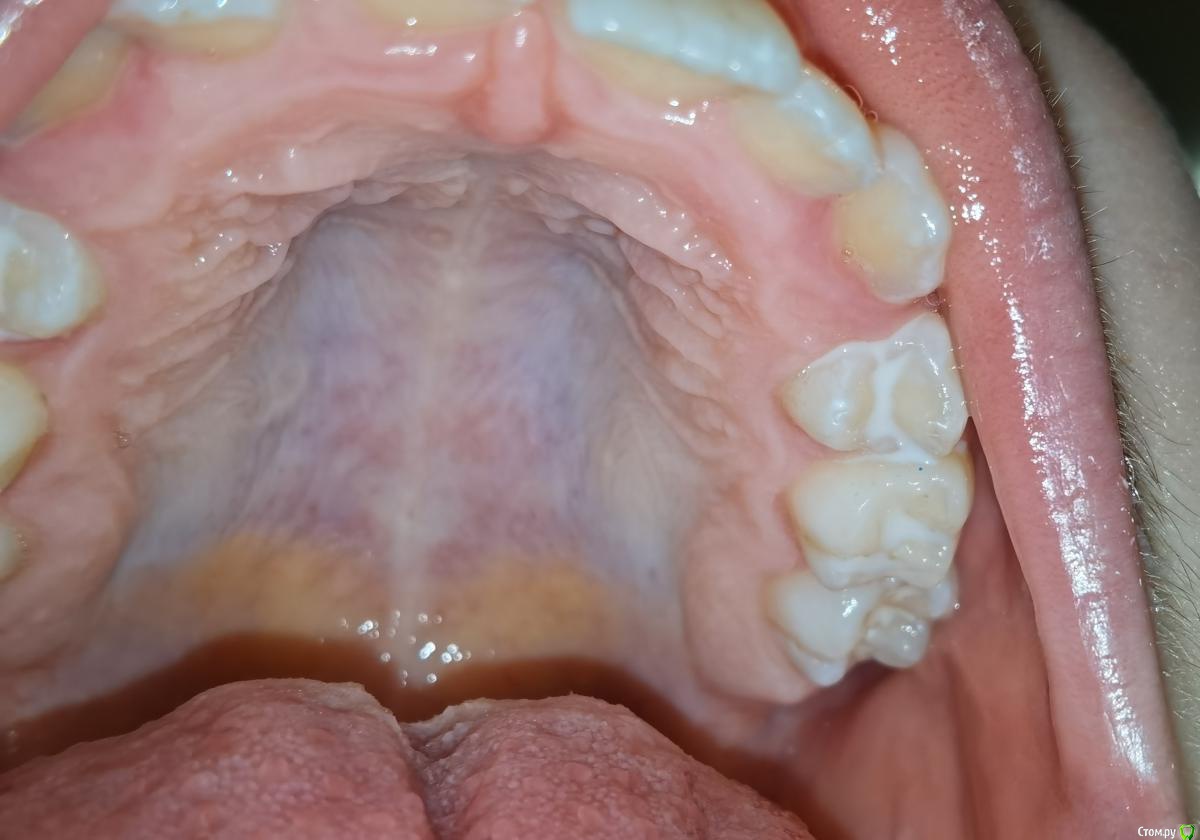

exxxtreme Опубликовано 6 июля, 2020 Поделиться Опубликовано 6 июля, 2020 Приветствую, делали раньше герметизацию зубов (некоторых, в основном молочных) ребенку у врача, все в целом было неплохо (кариеса под герметиком не было за года 4). В общем врачу доверяли. Вот на очередном приеме из-за глубоких фиссур где-то полгода назад прорезавшихся верхних четверок врач предложила сделать герметизацию (неинвазивную, т.е. как я понял без раскрытия фиссур) и их. Сделала, но я не посмотрел как, а дома глянул и слегка (мягко говоря) офигел. Загермечены были не только фиссуры, а и пришейки и герметик был вообще (как мост) между четверкой и молочной пятеркой. Т.к. мы пользуемся нитью, то нить и не проходила между 4 и 5. В общем возмущенный сходил к врачу, она слегка поудаляла герметик между 4 и 5 (пластинкой и бором-резинкой). Успокоила, что герметик в пришеечной это наоборот хорошо (тонкая эмаль), типа так и задумывала.А я по итогу все равно весь мозг себе проел - нужна ли эта герметизация или нет. тем более активно пользуемся зубной нитью, рано или поздно я часть герметика между 4 и 5 "сшибу" просто (нить там с трудом сейчас проходит), оставив непонятные контуры.Фото (до того как сделала промежуток между 4-5) прилагаю.Собственно вопросы:- нужна ли эта герметизация?- права ли врач?- если не нужна, можно ли как-то избавиться от этого герметика? http://print.ru/ger.jpghttp://print.ru/ger1.jpg Ссылка на комментарий